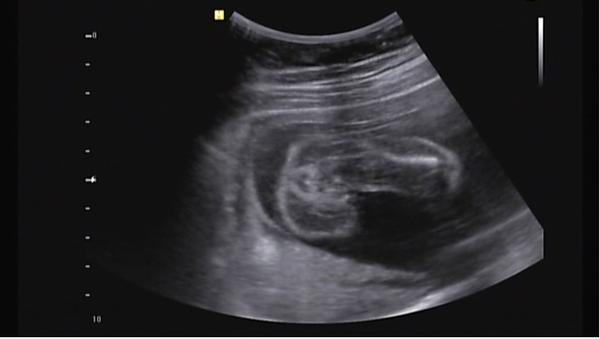

Je to holčička nebo chlapeček? Foto ultrazvuku

já si myslím že holčička 🙂 je tam kávové zrno 🙂

Dobré ráno, tak se taky přidávám se svou troškou do mlýna - co myslíte, holčička nebo chlapeček? 😀